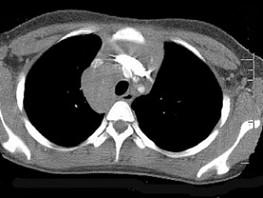

问题 7岁,男,发热、消瘦,数月前触及颈部淋巴结肿大,CT和MR检查如图,请选择最可能的诊断 ( )

选项 A、转移性淋巴肿大 B、胸腺瘤 C、结节病 D、淋巴结核 E、淋巴瘤

答案 E